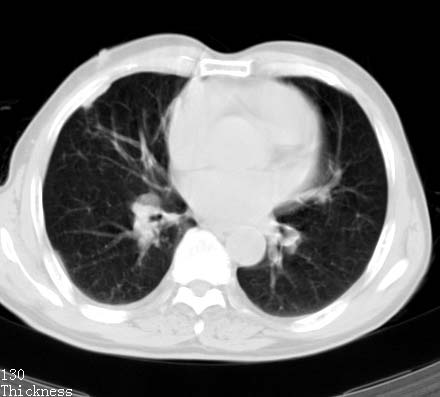

标题: CT14027:男性病人 71岁 咳嗽咳痰数周. [打印本页]

标题: CT14027:男性病人 71岁 咳嗽咳痰数周.

男性病人 71岁 咳嗽咳痰数周.诊断结核应该有保障吧!

结核是要考虑,但肺癌也不能排除.

高度怀疑肺癌,强烈要求纤支镜检查。